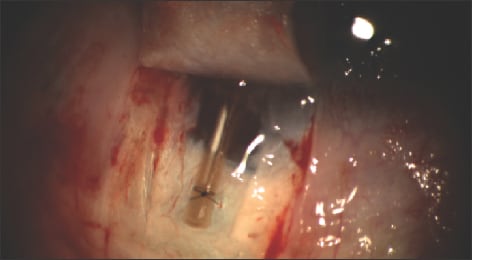

The inner flap is carried forward to the cornea. This may raise concerns about perforating the Descemet's window, which happens about 15% to 25% of the time for surgeons who are just starting to learn this procedure. Simply convert to a trabeculectomy if you do perforate. Rhein Medical (St. Petersburg, Fla.) makes a canaloplasty manipulator that is great for dissecting forward into the cornea (Figure 2).

Figure 2. Dissection forward into the cornea, using the Rhein canaloplasty manipulator.